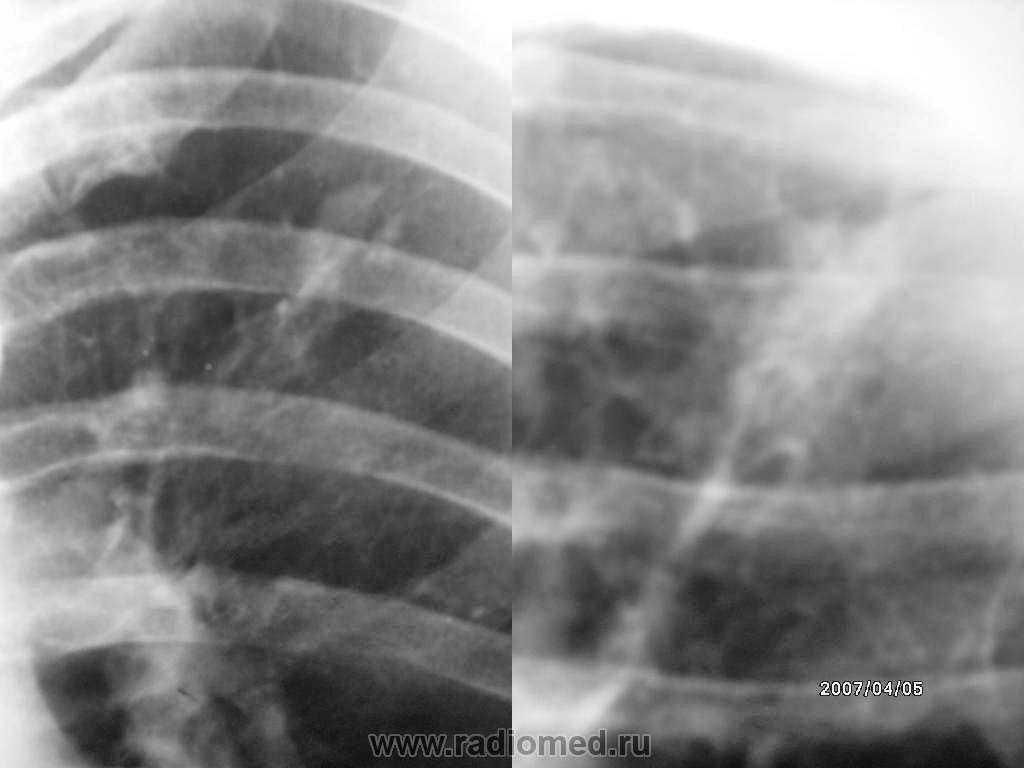

Мужчина пришел на дообследование после флюрографии (туберкулома слева). Жалоб нет. В 2003г. была правосторонняя пневмония.

Произведены снимки: обзорный и гиперлордоз.

Для шварты ужь больно "круглит", может архив был? Если нет то линейные томограммы для начала, там сразу ясно станет.

На первый взгляд, в общем все "довольно спокойно". Участок фиброза от очага к корню (по всей видимолсти, бывшая, преимущественно "бронхиальная" дорожка). Да и "аффект" в легочной ткани создает впечатление плотного.

Но при дальнейшем анализе - "структура " неоднородная.

А если проанализировать эту "пару", то без линейной томографии не обойтись.

Инфильтративный туберкулёз?

Спасибо большое коллеги! Вообще я написал- участок фиброза и меня весь день терзали сомнения ( вначале был полностью уверен, потом в конце рабочего дня взглянул еще раз и ....???). Сегодня запишу на томограмму и Вас позже обязательно проинформирую.